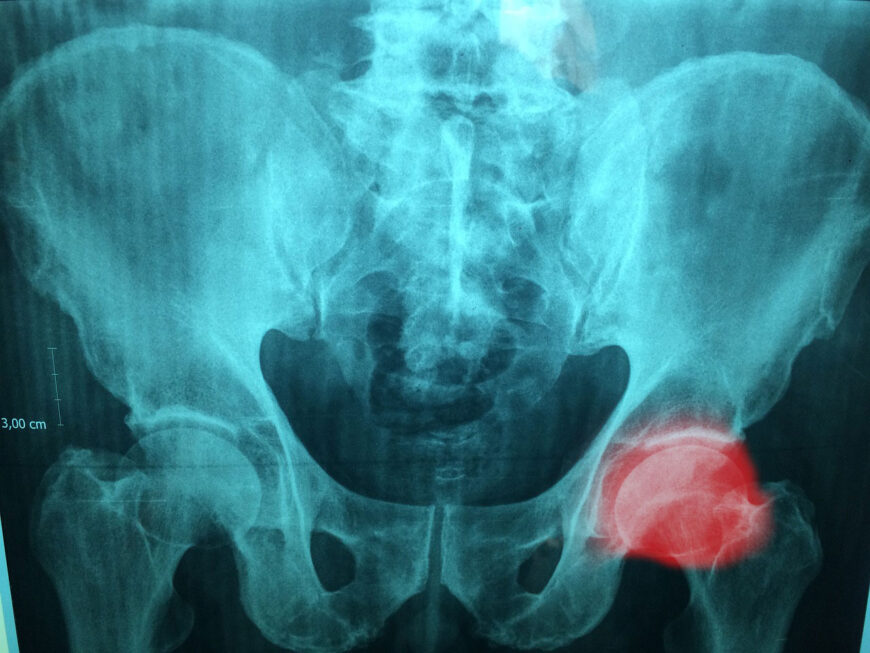

Hip Bursitis

Hip bursitis, also known as trochanteric bursitis, affects the bursa located on the outside of the hip joint. It can be caused by repetitive activities such as running or standing for prolonged periods. The symptoms may include pain and tenderness on the outer side of the hip.

Treatment

Treatment for hip bursitis involves rest, ice, and anti-inflammatory medications. Physical therapy may be prescribed to improve hip strength and flexibility. In some cases, corticosteroid injections or aspiration of the bursa may be necessary.